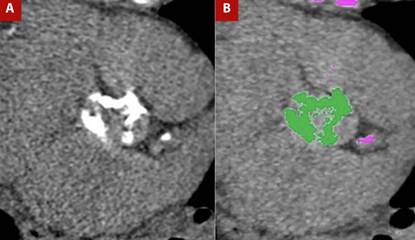

Valvular calcium is assessed by non-contrast CT, typically performed at 120-140 kV (although other manufacturers provide different specifications), with a matrix size of 512 × 512, tube current adjusted according to body weight, slice thickness of 2.5-3 mm, images acquired during diastole, and calcifications defined as areas with density ≥130 Hounsfield units (HU). This protocol is known as the Agatston method. Based on HU values, findings are stratified into four groups: group 1, 130-199 HU; group 2, 200-299 HU; group 3, 300-399 HU; and group 4, ≥400 HU. The group number is multiplied by the area (cm²) of the lesion, and the values for all lesions are summed to obtain the calcium score, expressed as Agatston units (AU; Figure 2). Lesions in valve cusps and the annulus should be included, whereas calcifications of the left ventricular outflow tract, mitral valve, and proximal coronary arteries must be excluded to avoid overestimation. 15,16

Figure 2 A) Non-contrast cardiac-gated CT in the aortic valve plane for calcium assessment and B) Post-processing for calcium quantification. Marked calcifications are present in the aortic valve leaflets, yielding a calcium score of 2889 Agatston units, highly suggestive of severe aortic valve stenosis.